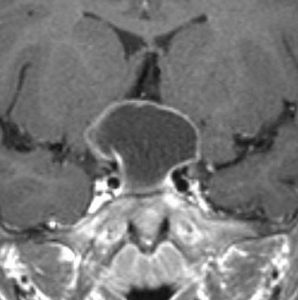

成人の第3脳室内部に局在する頭蓋咽頭腫です。経脳梁法で両側のモンロー孔から全摘出しました。下垂体組織は残っています。これは乳頭状頭蓋咽頭腫と呼ばれるもので,成人にしか発生しません,のう胞がなく石灰化もないのが大きな特徴です。境界が明瞭で柔らかく摘出が簡単なタイプとして知られています。この患者さんも術後に下垂体機能不全も視床下部障害も生じませんでした。